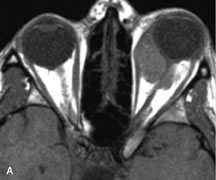

Muscle Disorders

Extraocular muscle enlargement in patients with thyroid-associated orbitopathy is demonstrated equally well with CT and MRI studies. However, the superior tissue contrast on MR images reveals better details of the relationships of the optic nerve to the thickened muscles at the orbital apex (Fig. 16).50 In addition, MRI may be able to differentiate between muscles that are enlarged as a result of edema and active inflammation and those enlarged because of fibrosis by their T2 relaxation times.21 Quantitative MRI was not found to be accurate in predicting the success of low-dose orbital irradiation.51 However, a muscular index relating the diameters of the rectus muscles to the bony orbital dimensions was useful in predicting optic nerve compression.52

Fig. 16. A-C, T1-weighted MR scans obtained with a high-resolution surface coil demonstrate fusiform enlargement of the extraocular muscles. The medial, lateral, and inferior rectus muscles are especially involved. Note the relative sparing of the tendinous insertions, a finding characteristic of this disease process, as well as fatty infiltration of the lateral and inferior rectus muscles. There is marked proptosis, best visualized on the sagittal image (A), and mild crowding of the optic nerve at the orbital apex.